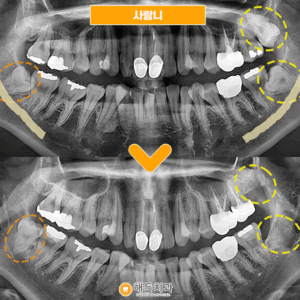

사랑니발치 환자분의 간식선물🍩

안녕하세요~ 해든치과입니다! 오늘은 사랑니 발치하신 환자분께서 사랑니 때문에 걱정이 많았는데 안아프게 잘 뽑아주셔서 감사하시다며 간식선물을 해주셨습니다ㅎㅎ     잇몸뼈 안쪽으로 매복되어 있던 사랑니라 집 근처 치과에서 큰 치과에 가야한다고 들으시고 해든치과에 내원해주셨습니다     다행히 사진촬영해보니 발치가 가능한 정도이셔서 해든치과에서 사랑니를 발치하셨습니다🤗   큰병원에 가라니 막막하고 무서운 더보기…